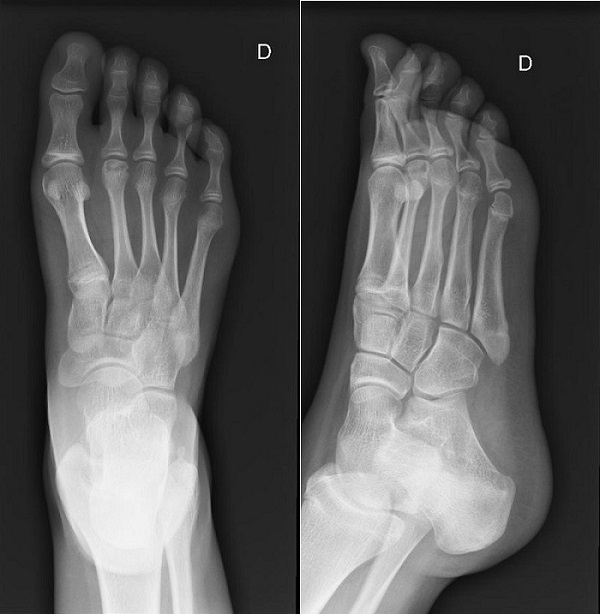

Teniendo en cuenta este caso clínico, se plantea el diagnóstico diferencial entre las patologías musculoesqueléticas de origen inflamatorio y aquellas que atienden a una etiología puramente mecánica. En aras de dilucidar el diagnóstico definitivo, y debido al tiempo de evolución del dolor, se decide solicitar analítica de sangre, que resulta ser normal, y radiografía simple del tobillo-pie (anteroposterior y lateral) (Fig. 1).

Figura 1. Radiografía simple del tobillo-pie (anteroposterior y lateral), donde se confirma la presencia de una patología de origen mecánico, sito en el segundo metatarsiano: enfermedad de Freiberg (o Kohler II)

El informe radiológico confirma la presencia de una patología de origen mecánico, sito en el segundo metatarsiano: enfermedad de Freiberg (o Kohler II). Se trata de una osteocondrosis, causante de metatarsalgia y cojera en el paciente adolescente (típico de mujeres y de predominio unilateral), cuyo diagnóstico es clínico y su confirmación se realiza a través de la radiografía simple, siendo la imagen patognomónica: esclerosis del hueso subcondral y cambios quísticos en la cabeza del segundo metatarsiano.